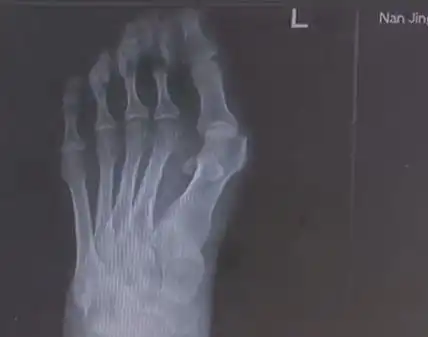

爱穿高跟鞋的女性一定要小心,拇指外翻堪比裹脚不可忽视

作为一个女生,脚拇指外翻是一种怎样的体验